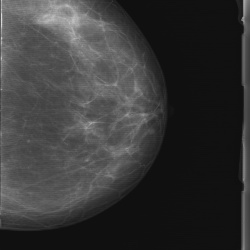

Женщина 66лет. Жалоб нет.